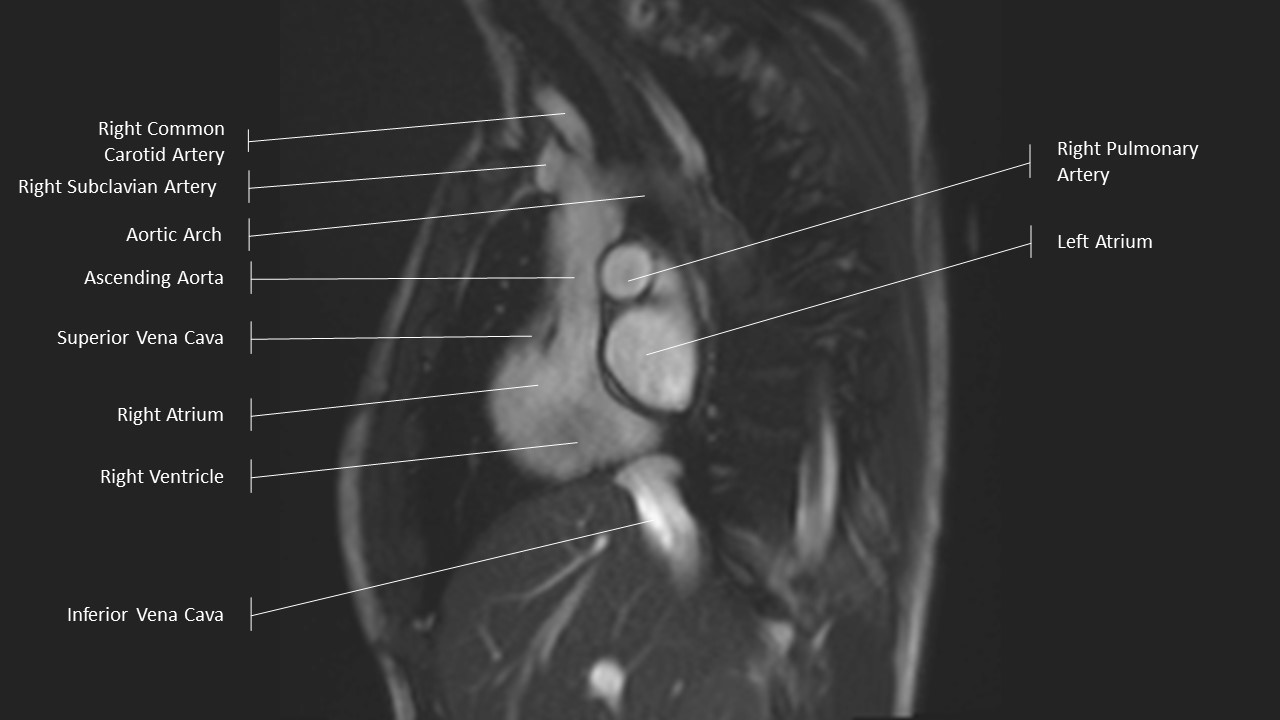

Aortic Arch Series